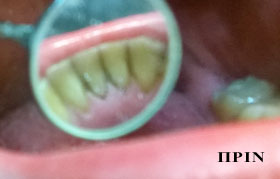

PHOTO GALLERY